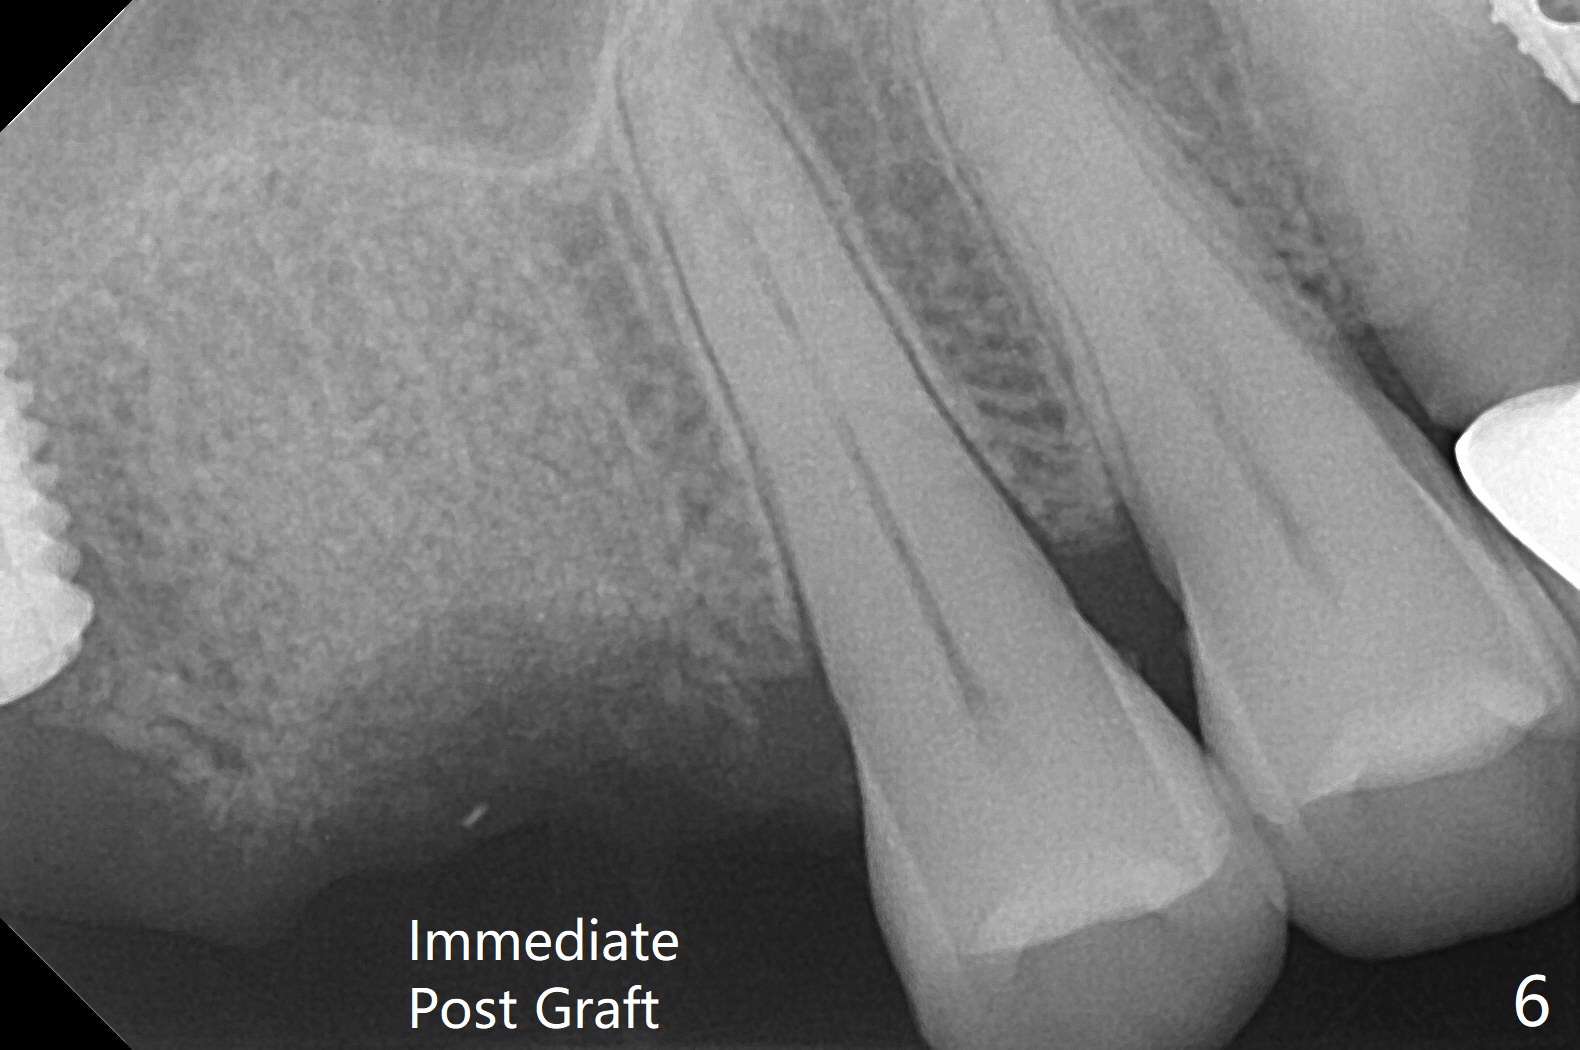

拔牙也有困难,虽然十分松动,但是无法脱位,研究两年前CT,牙长,弯曲(图),分根后才完成拔除,骨块剪成三块,分别插入三个牙槽窝(图六),覆盖PRF膜和压扁的胶原塞,缝合。